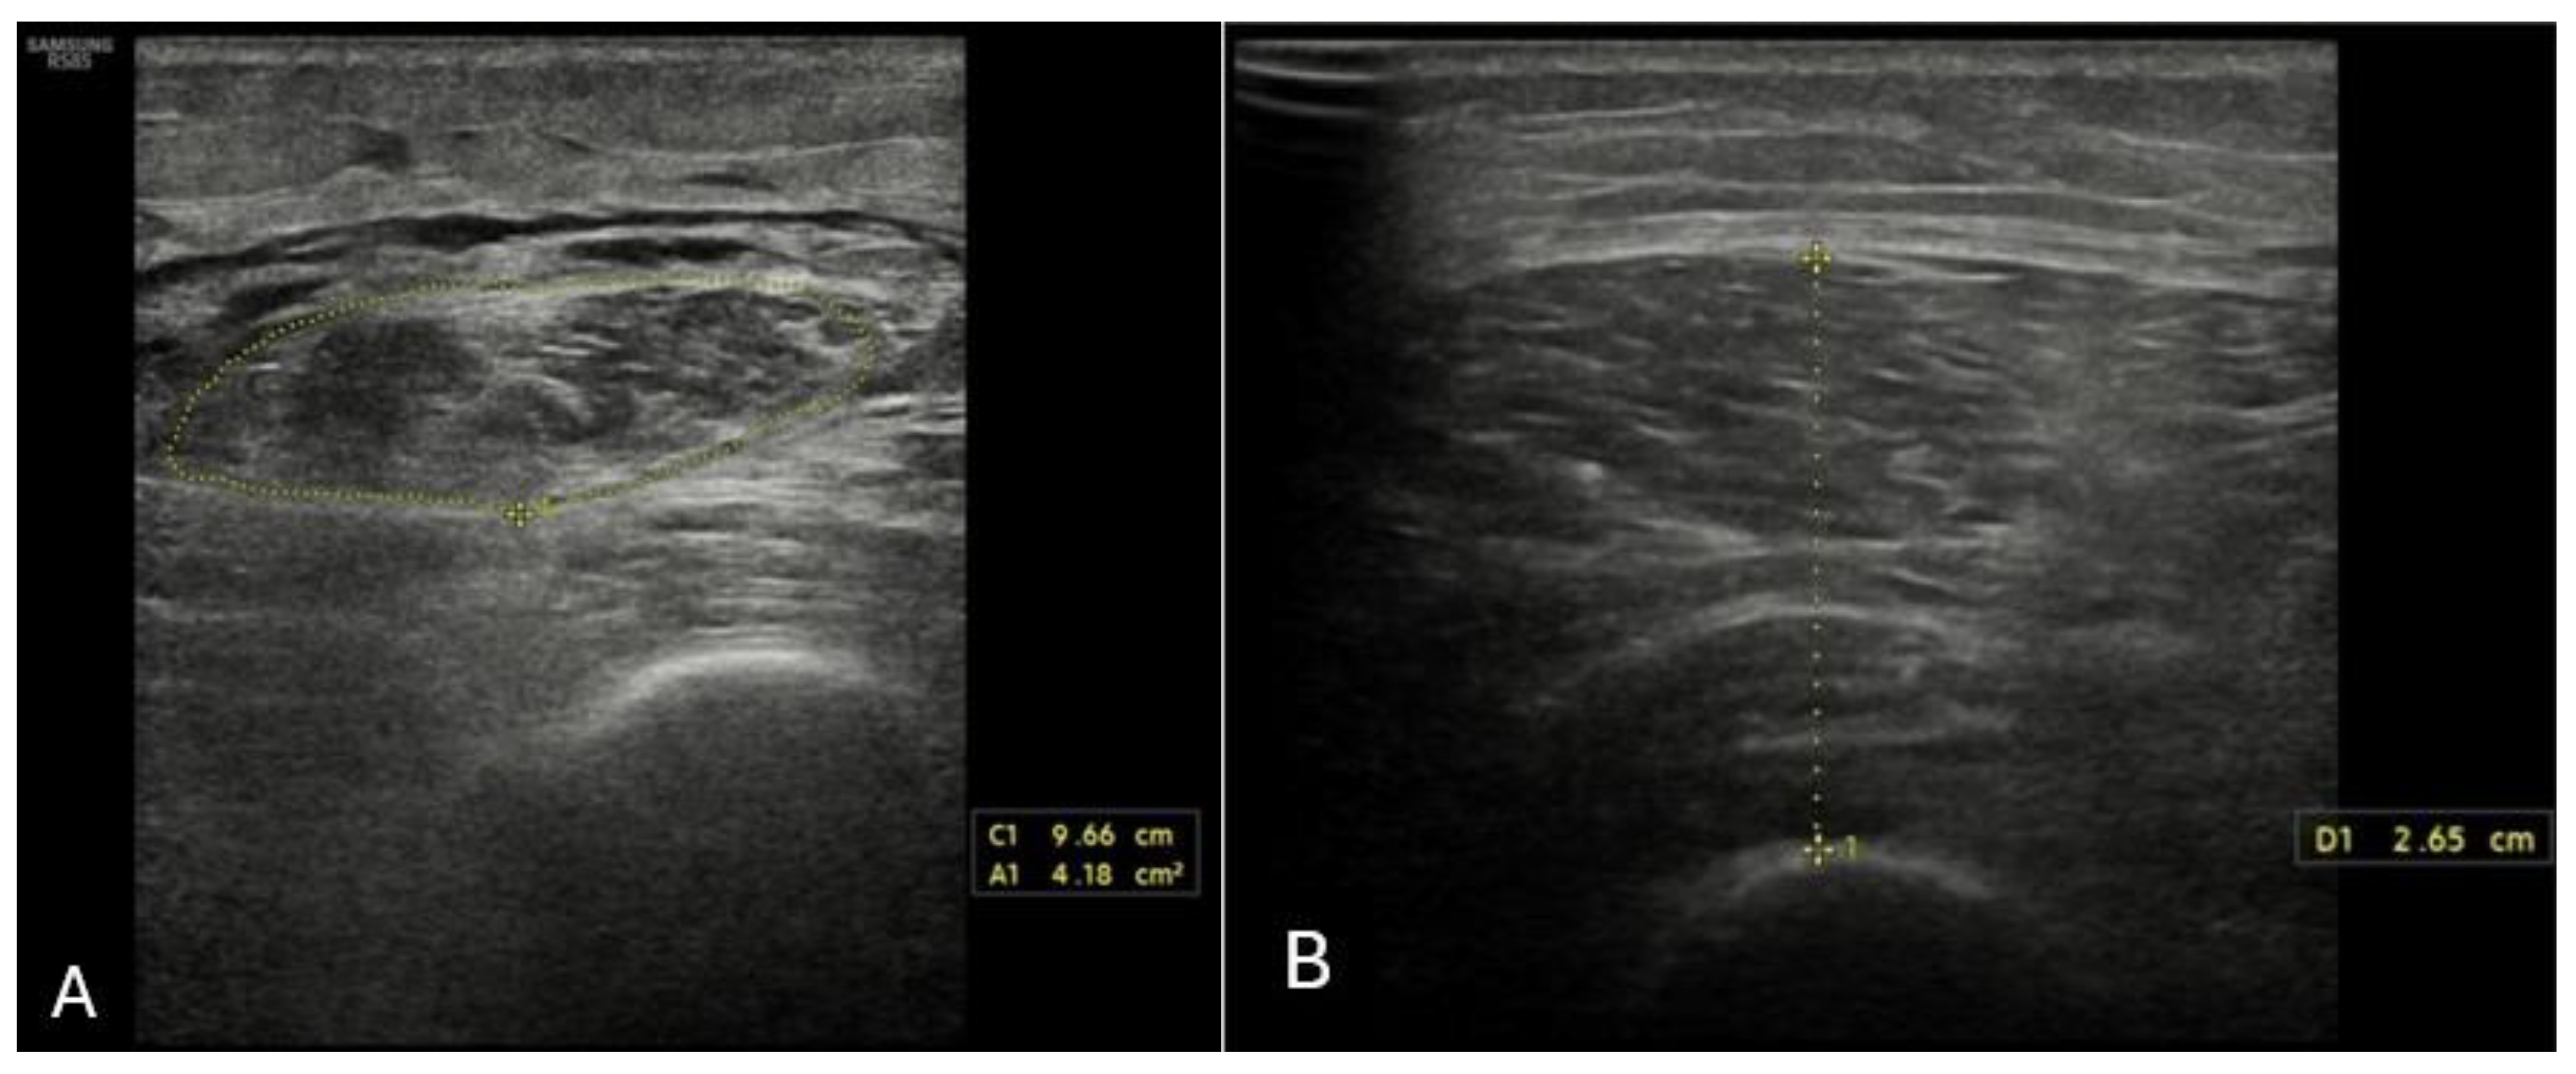

4.6. Ultrasound Assessment of Skeletal Muscle Tissues

- Gödiker, J.; Schwind, L.; Jacob, T.; Böhling, N.; Groba, S.N.R.; Kimmann, M.; Meier, J.A.; Peiffer, K.; Trebicka, J.; Chang, J.; et al. Ultrasound-Defined Sarcopenia Independently Predicts Acute Decompensation in Advanced Chronic Liver Disease. J. Cachexia Sarcopenia Muscle 2024, 15, 2792–2802. [Google Scholar] [CrossRef] [PubMed]

- Becchetti, C.; Berzigotti, A. Ultrasonography as a diagnostic tool for sarcopenia in patients with cirrhosis: Examining the pros and cons. Eur. J. Intern. Med. 2023, 116, 27–33. [Google Scholar] [CrossRef] [PubMed]

- Tandon, P.; Low, G.; Mourtzakis, M.; Zenith, L.; Myers, R.P.; Abraldes, J.G.; Shaheen, A.A.M.; Qamar, H.; Mansoor, N.; Carbonneau, M.; et al. A Model to Identify Sarcopenia in Patients With Cirrhosis. Clin. Gastroenterol. Hepatol. 2016, 14, 1473–1480. [Google Scholar] [CrossRef]

- de Luis Roman, D.; García Almeida, J.M.; Bellido Guerrero, D.; Rolo, G.G.; Martín, A.; Martín, D.P.; García-Delgado, Y.; Guirado-Peláez, P.; Palmas, F.; Pérez, C.T.; et al. Ultrasound Cut-Off Values for Rectus Femoris for Detecting Sarcopenia in Patients with Nutritional Risk. Nutrients 2024, 16, 1552. [Google Scholar] [CrossRef] [PubMed]

- Ciocîrlan, M.; Mănuc, M.; Diculescu, M.; Ciocîrlan, M. Is rectus abdominis thickness associated with survival among patients with liver cirrhosis? A prospective cohort study. Sao Paulo Med. J. 2019, 137, 401–406. [Google Scholar] [CrossRef]

- Hari, A.; Berzigotti, A.; Štabuc, B.; Caglevič, N. Muscle psoas indices measured by ultrasound in cirrhosis—Preliminary evaluation of sarcopenia assessment and prediction of liver decompensation and mortality. Dig. Liver Dis. 2019, 51, 1502–1507. [Google Scholar] [CrossRef]